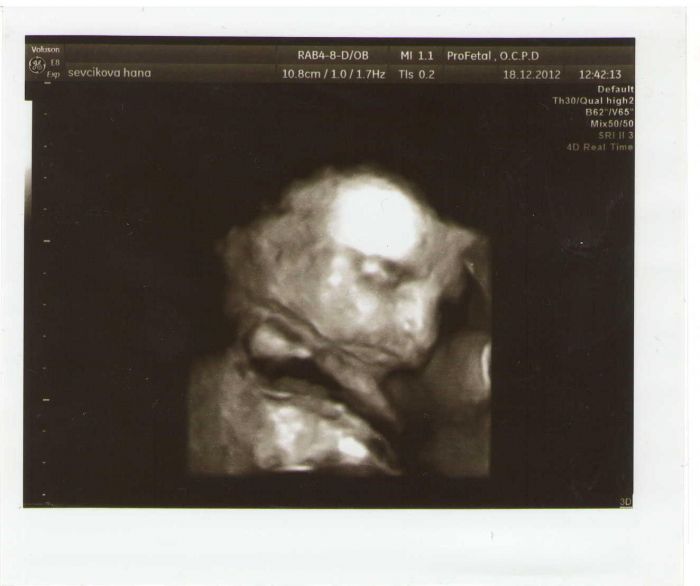

Jinak dnes jsem byla na tom 3D UZ. Maťa dělal netykavku. Pindíka ukazoval jako zkušený exhibicionista ale obličejík si bránil jako boxer.

Byla legrace, ale i přesto jsme ukořistili a nějaké záběry jeho obličejíku. Byl tam se mnou manžel a jak ho viděl, tak se smál. Má první slova byla "ježišikirste on má nos jako ty!"

a následoval záchvat smíchu, přičemž mi doktor řekl, že jestli se budu takhle smát celou dobu, tak z toho videa (mám DVD 15 minut) nic mít nebudu. Nakonec jsem byla ujištěna, že děti se s takovým nosem nerodí .. no to si povíme :-D je to kluk tak je to jedno, hlavně ať je zdravý, bude prča.